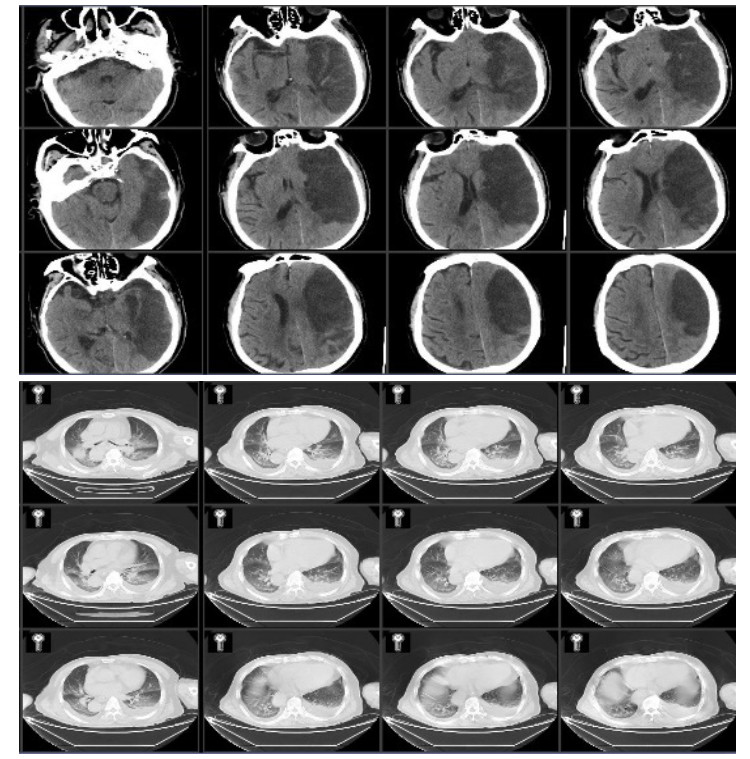

病例2,男性,80岁,因“突发右侧肢体无力1周,加重伴意识障碍1 d”由外院转入我院。外院头颅CT示左侧额颞叶片状低密度灶,诊断大面积脑梗死。头颅CTA示左侧颈内动脉及大脑中动脉部分闭塞,急诊溶栓治疗无效。既往有高血压病史20年,无冠心病房颤病史。入院查体:生命体征平稳,体温37.8 ℃,GCS 2-5-1,双瞳等大等圆,光敏,左侧肢体有不自主活动,右侧肢体无活动,右侧巴氏征阳性。入院诊断为左额颞大面脑梗,肺部感染,高血压病。入院后头肺CT见图 3。

| 图 3 入院患者头颅和肺CT |